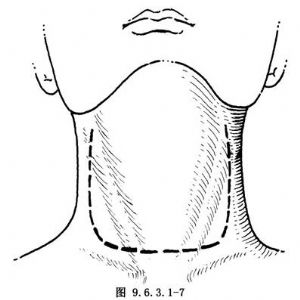

U形切口,上自一側乳突尖下方向下內側走向,達環甲膜平面中線,向對側延長至乳突尖下方(圖9.6.3.1-7)。此切口暴露清楚,適於行喉全切除術及頸淋巴結廓清術。